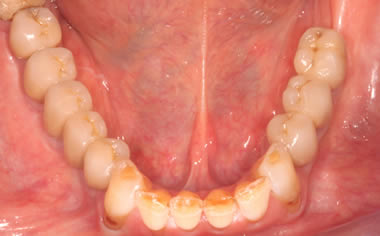

More back teeth replaced by dental implants

Case Three (2 images)

Case Four (4 images)